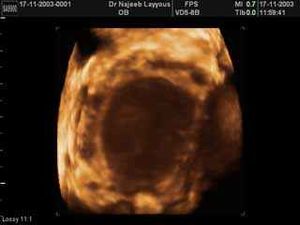

- جهاز الألتراساوند المهبلي: ممكن أن يكشف عن وجود أكياس دموية على المبيضين.

- الرنين المغناطيسي MRI: يمكن أن يكشف عن أكياس الدم ووجود الأنسجة الهاجرة متناثرة في الأمعاء والمثانة ووجود التصاقات حول المبيض.